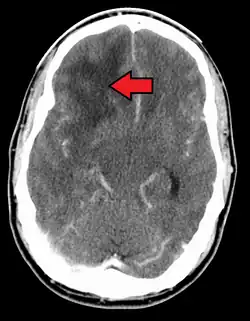

![]() | |

| A coronal view (from the back of the head) of a contrast-enhanced MRI revealing a glioblastoma in a 15-year-old boy | |